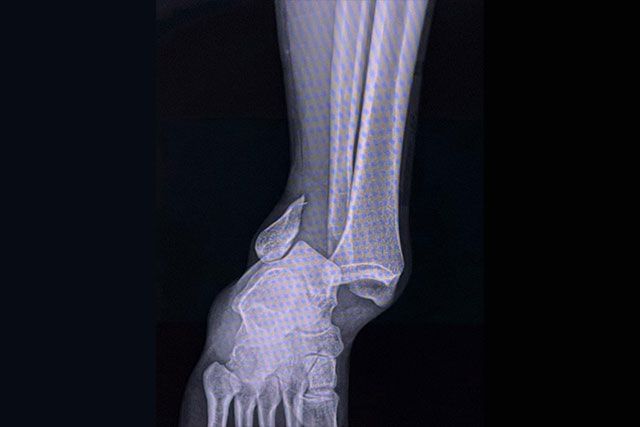

- Esguinces de tobillo y rodilla

- Fracturas por estrés o impacto

Se realiza un abordaje integral que incluye diagnóstico clínico y por imagen (rayos X, ultrasonido, resonancia), plan terapéutico individualizado y asesoría para el retorno seguro al deporte.